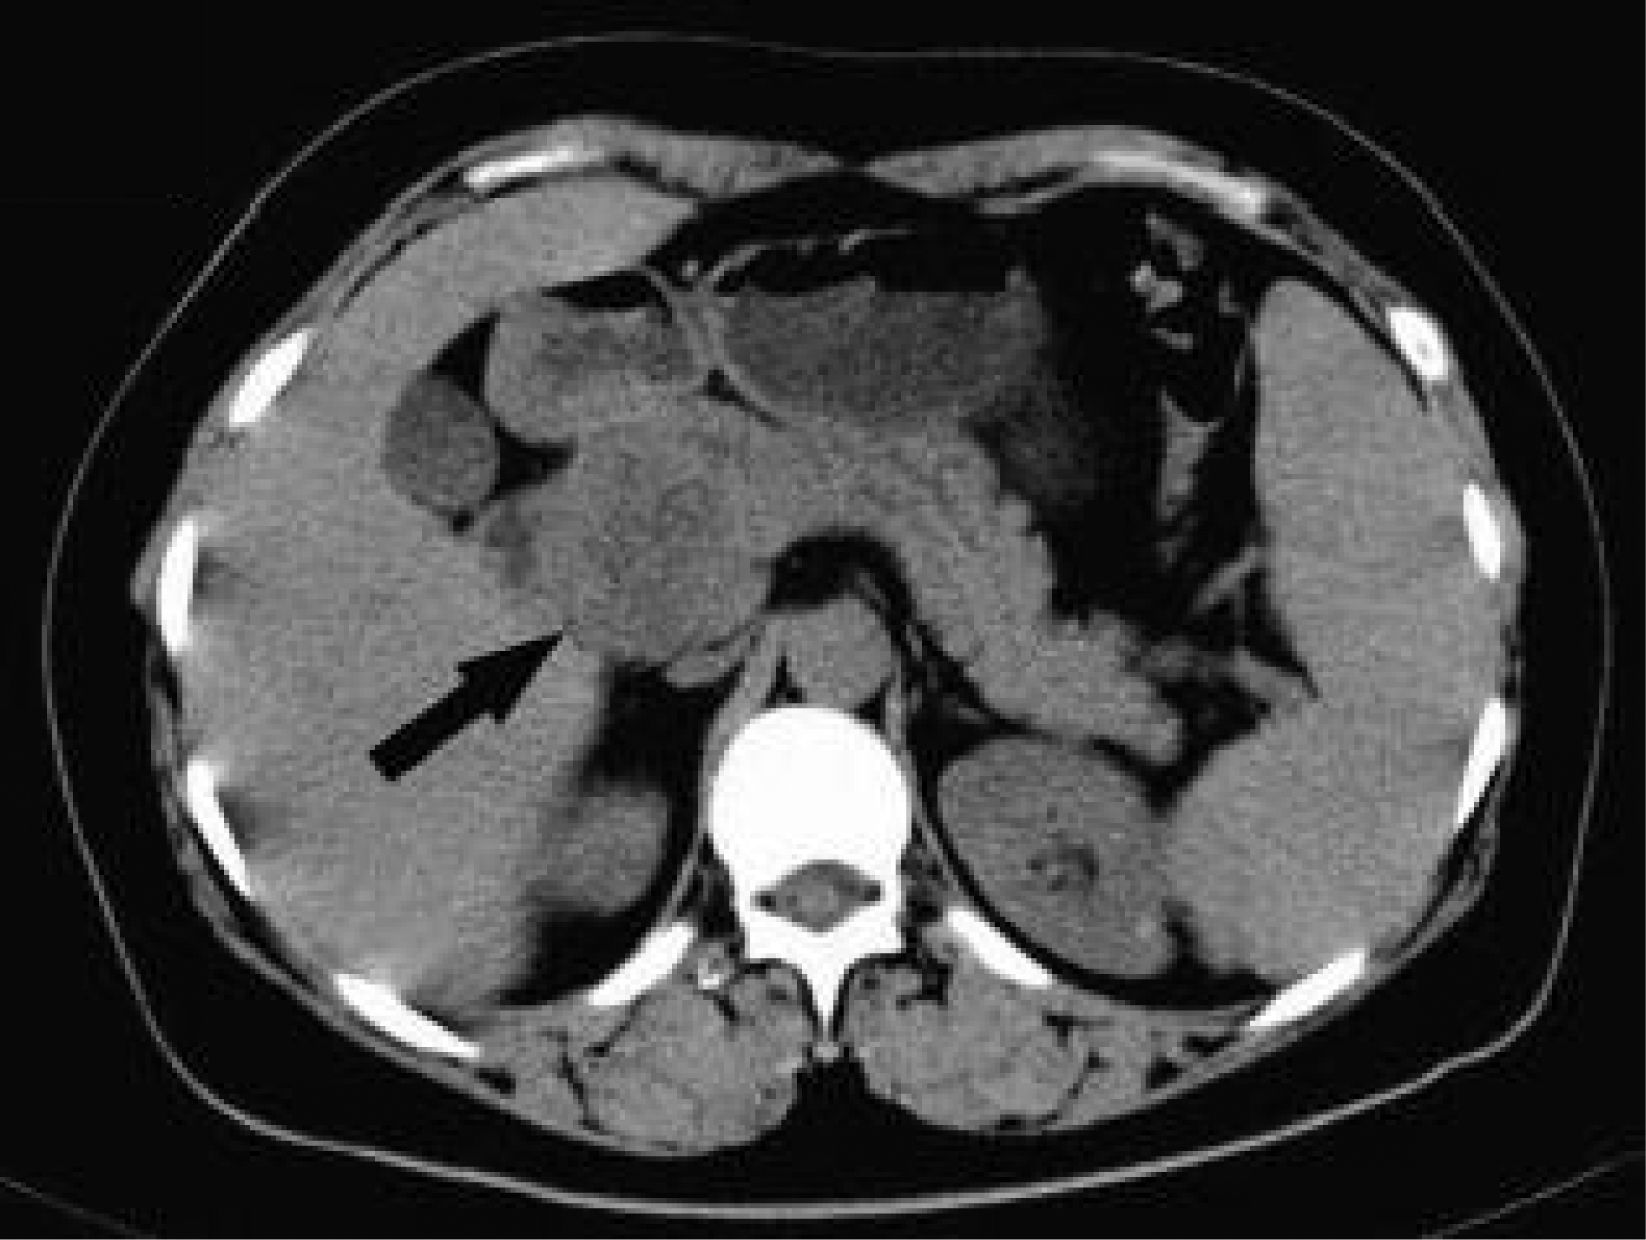

Revista Española de Anestesiología y Reanimación Paraganglioma pancreático incidental

Paraganglioma pancreático incidental

Incidental pancreatic paraganglioma